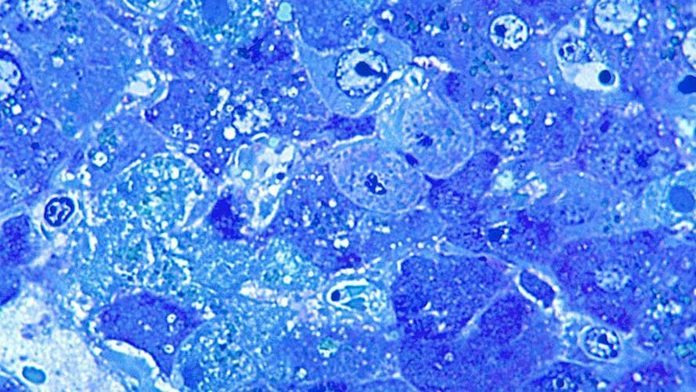

Lassa fever is caused by Lassa virus. Prior to these latest cases, there have been eight imported to the UK since 1980.

About 80% show no symptoms, while others experience a fever with aches and pains that can progress to headaches, vomiting and diarrhoea.

In severe cases there may be facial swelling, fluid in the lung cavity, bleeding from the mouth, nose, vagina or gastrointestinal tract and low blood pressure.

Deafness occurs in 25% of patients who survive the disease.